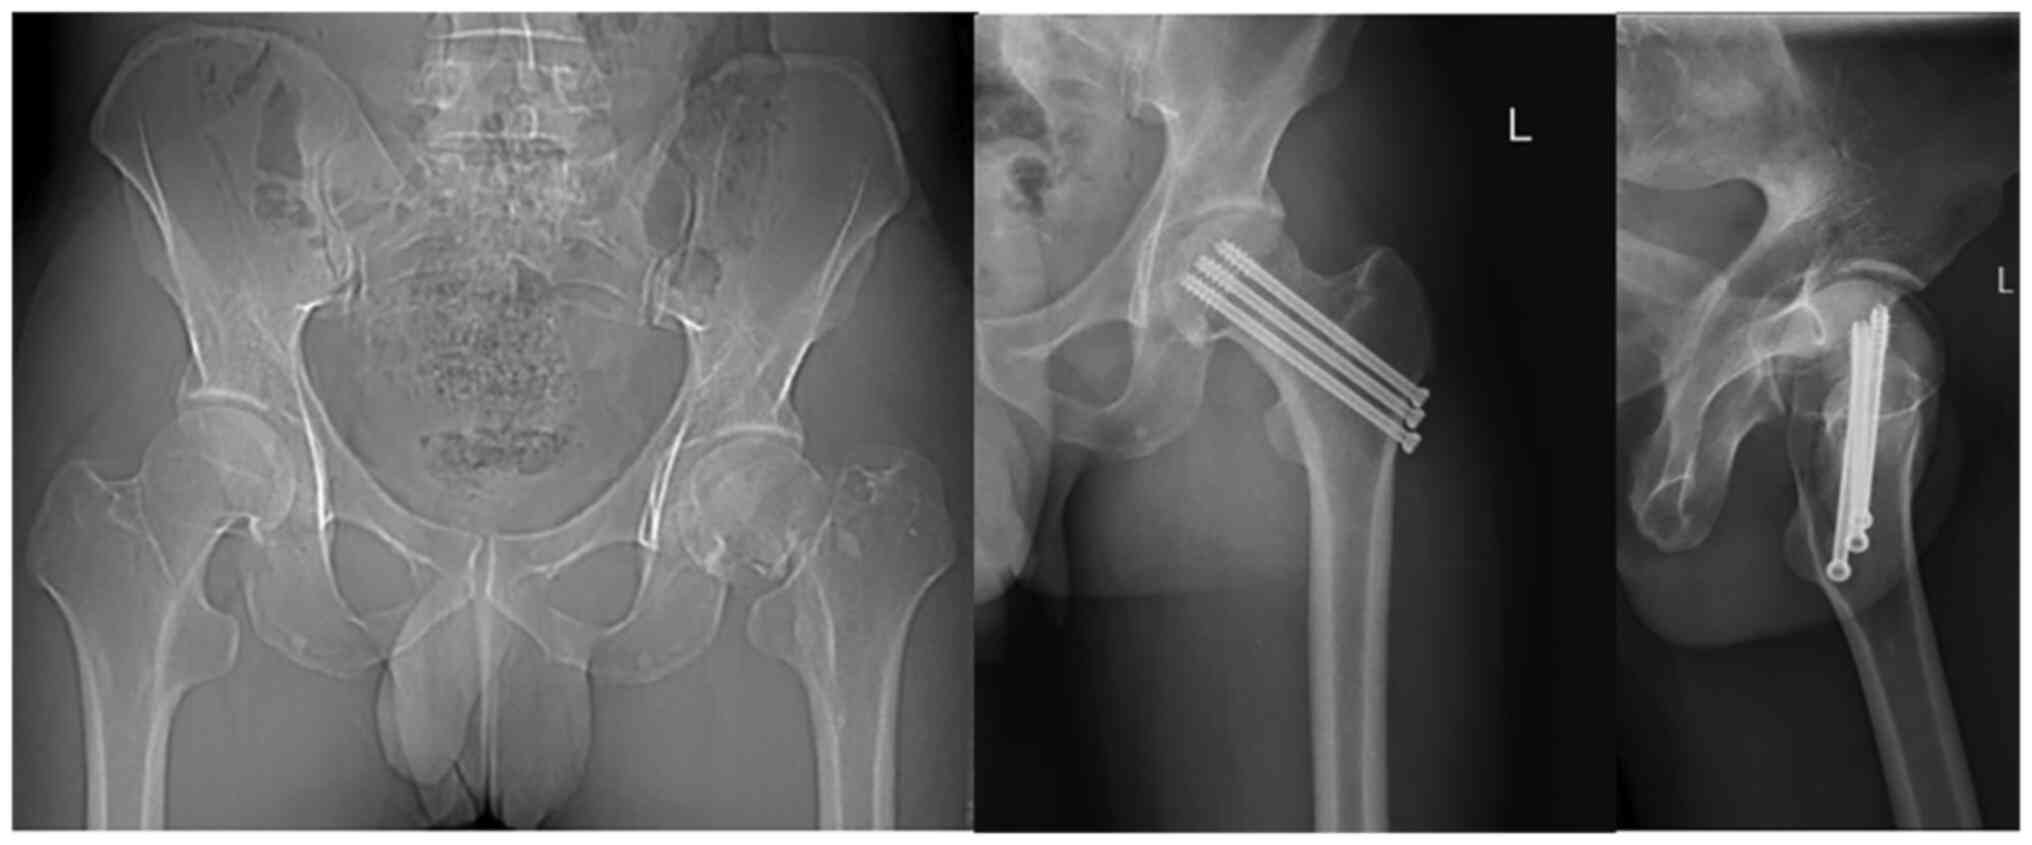

After surgery, the patients were treated with pain relief, anti-infection and anticoagulation therapies. On the second day after surgery, the patients could perform lower limb functional exercises in a sitting position. Full weight-bearing of the affected limb was avoided for three months, and gradual weight-bearing to full weight-bearing was performed with the help of a walking aid according to fracture healing during follow-up examinations. Patients in groups A and B visited the First Affiliated Hospital of Nanjing Medical University (Jiangsu Province Hospital) for regular follow-up examinations at 1, 2, 3, 6 and 12 months after surgery. At these follow-ups, anteroposterior and lateral hip radiographs (digital radiography equipment; Ysio Max Smart Speed MAX Platform; Siemens Healthineers) were performed and used to assess fracture healing, and a functional assessment of the hip joint was performed. Typical cases in both groups are shown in Figs. 1 and 2.

Figure 1

Case from group A: Liu, male, 76 years old. The left panel shows the patient with a subcapital femoral neck fracture on a preoperative X-ray; the middle and right panels show the postoperative femoral neck fracture, at the last follow-up visit, 12 months after surgery. Anteroposterior X-ray and lateral radiographs with three cannulated screws with inverted triangular distribution demonstrate that the fracture has already healed.